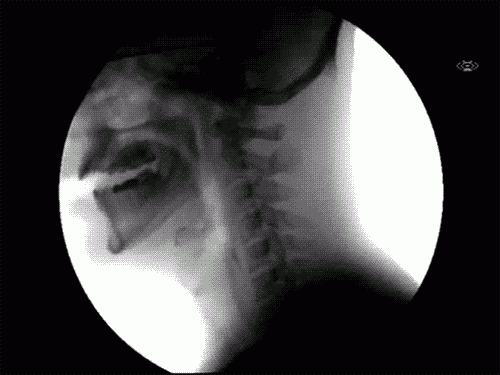

Что происходит, когда вы глотаете